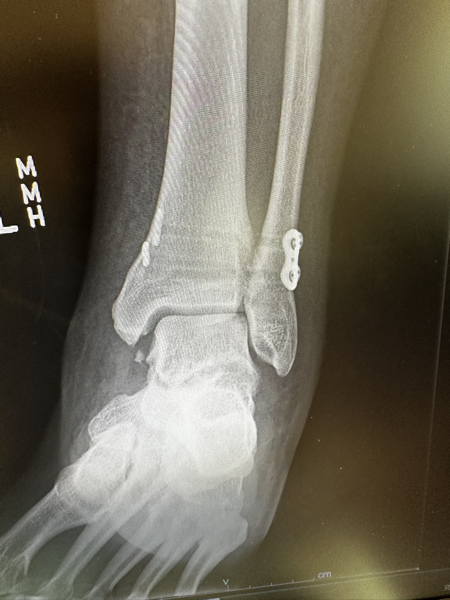

X-Ray of a fractured ankle.

Thankfully, the Fire Department picked me up in no time flat and by 8 AM I was in the emergency room.  X-rays showed that I had broken my tibia down at the ankle joint s well as my fibula up closer to my knee.  By 11 AM I was being rolled into surgery, with a slight worry that my surgeon my be a bit annoyed at being brought in on Christmas Day.  However, the surgery went well after a couple of days, I was sent home to start what would be a long recovery . . .

X-Ray of a fractured ankle with hardware installed.